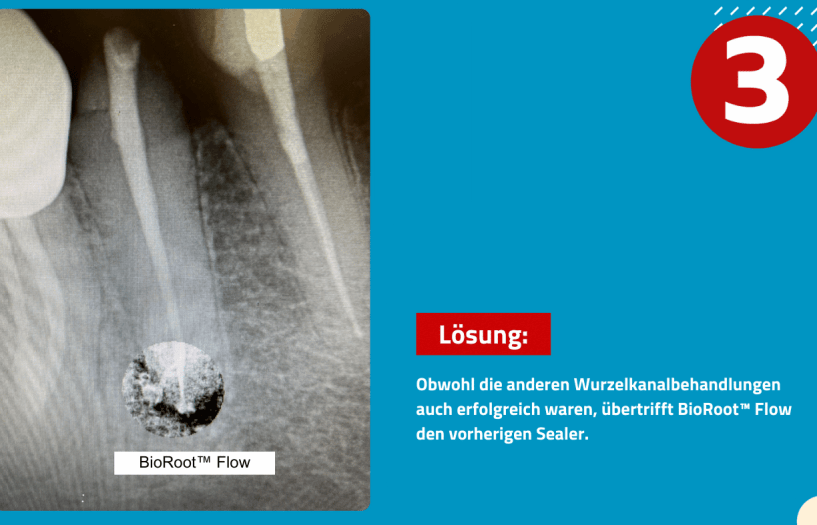

Beachten Sie den Vergleich zwischen den drei Wurzelkanälen. Der mittlere Zahn wurde mit BioRoot™ Flow versiegelt.

Lösung:

Obwohl die anderen Wurzelkanalbehandlungen auch erfolgreich waren, übertrifft BioRoot™ Flow den vorherigen Sealer.